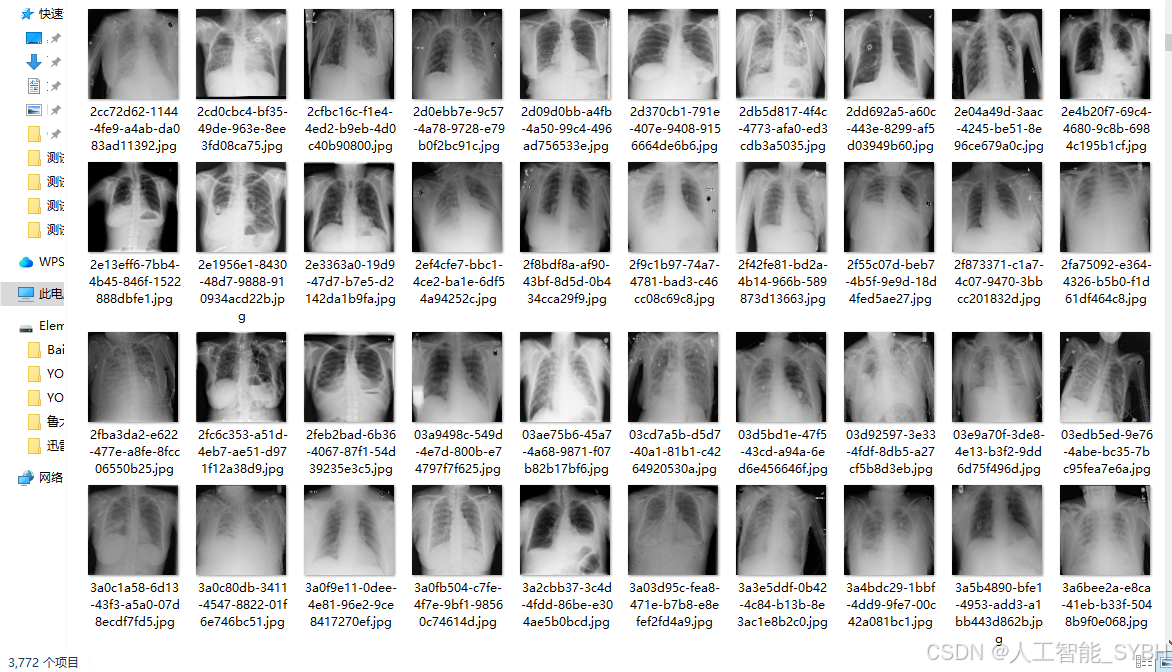

三、数据集介绍

数据集名称: 肺炎检测数据集

数据集内容:

数据集规模:

训练集: 3772张图像

验证集: 539张图像

测试集: 1078张图像

数据来源:

数据集通过收集医院中的胸部X光片构建,涵盖了不同年龄段、性别和病情的患者,以确保模型的泛化能力。

数据集特点:

多样性: 数据集包含不同患者的胸部X光片,覆盖了多种病情和拍摄条件。

-

高质量: 图像分辨率高,标注精确,适合深度学习模型的训练。